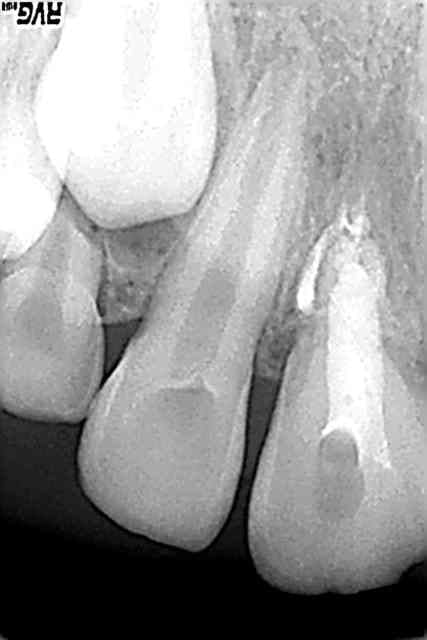

ploc

14/09/2007 à 18h05

rappel:choc avec expulsion et réimplantation de 11 en aoôut 2006 en milieu hospitalier

il a mainteant 9 ans et 5 mois

ankylose :ok, rien de nouveau

mes questions: les incisives du bas?

qu'en pensez vous?

il n'a pas de retard dentaire qd on regarde les autres dents mais les apex ne st pas fermés et les racines courtes surtout 31 41

ankyloses aussi?

aucun signes cliniques,repondent au froid

heeeeeeeeeeeeelp